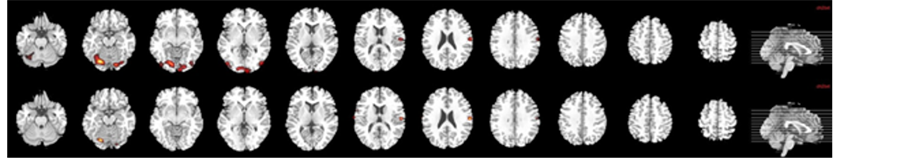

During the processing of neutral faces compared with baseline (12 foci), there was a significant activation in the following brain areas: temporal areas (left superior and middle temporal gyrus), visual areas (left calcarine, left lingual gyrus, left lateral occipitotemporal gyrus) and left pre- and postcentral gyri (cluster-level Familywise Error Rate FWE correction (p < 0.05); Table 2, Figure 2(a)).

Figure 2. Brain map of neural activation in response to both neutral (a) and 100% fearful facial (b) expressions compared with fixation cross in B.D. in acute stroke before and after rehabilitation program.

2.2.2. Processing 100% Fearful Faces

The response to fearful stimuli recruited the following areas with significantly increased BOLD signal (9 foci): visual areas (left calcarine, left lingual gyrus, left fusiform gyrus), left pre and postcentral gyri and right cerebellum (cluster-level FWE correction (p < 0.05); Table 2, Figure 2(b)).

The processing of neutral faces compared with baseline (8 foci) showed increased neural activation in the following regions: visual areas (left lingual gyrus, left fusiform gyrus), left precentral and right postcentral gyri and right cerebellum (cluster-level FWE correction (p < 0.05); Table 2, Figure 2(a)).

2.3.2. Processing Fearful Faces

After therapy of B.D., significantly increased brain activation was reported in the following brain areas (4 foci): bilateral postcentral gyrus, right cerebellum and left lingual gyrus (cluster-level FWE correction (p < 0.05); Table 2, Figure 2(b)).

Hence, before therapy of B.D. recruitment was larger in the left hemisphere, both with neutral and fearful faces.

In response to neutral faces, visual cortex was significantly activated including calcarine and fusiform gyrus. Before treatment was provided, perception of 100% fearful expressions recruited cerebellum, precentral gyrus and visual regions but not amygdala.

B.D. showed fewer post-therapy activation maps compared with pretherapy ones and more significantly activated pre- and postcentral gyrus and right cerebellum in response to 100% fearful faces.

Interestingly, neither amygdala nor visual areas including fusiform gyrus and calcarine were activated as the response to fearful stimuli after therapy completed.